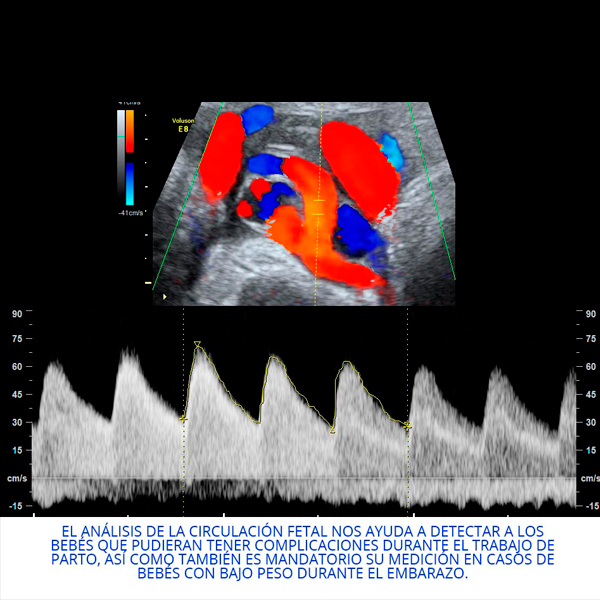

Actualmente realiza un Doctorado Internacional en Medicina Fetal avalado por las universidades de KU Leuven (Bélgica), Universidad de Barcelona (España) y la Universidad de Lund en Suecia, tres instituciones líder en el segmento de la medicina fetal a nivel mundial.